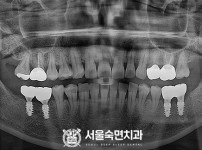

임플란트-전후사진4